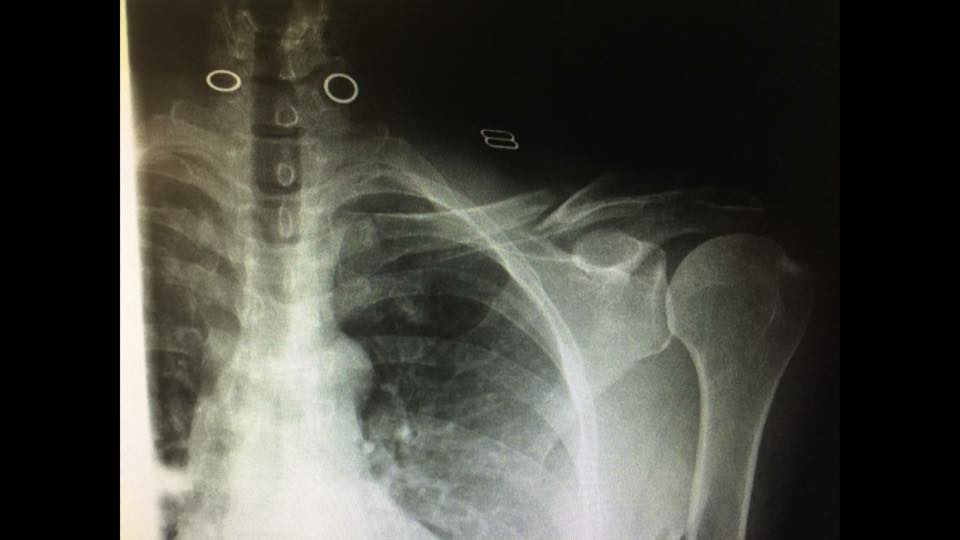

Lori broken clavicle Published April 19, 2017 at 960 × 540 in Mulholland Double Century – That Became a Century Instead